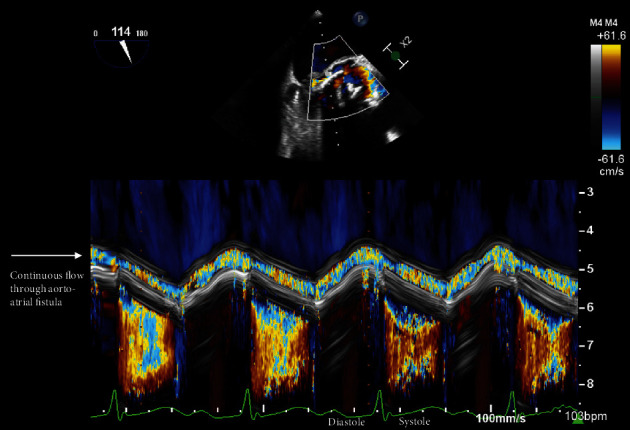

主动脉心房瘘是感染性心内膜炎的一种罕见并危及生命的并发症,通常通过观察主动脉和心房之间的连接并伴有连续血流来诊断。一名患者患有生物人工瓣膜和原生瓣膜肠球菌性心内膜炎,并伴有多种并发症,其中包括经食道超声心动图彩色 M 型诊断出的主动脉心房瘘。我们回顾了主动脉心房瘘的特征,并利用这个病例展示了如何利用 M 模式在诊断不确定的情况下提供更好的时间分辨率。

Aorto-atrial fistula is a rare and life-threatening complication of infective endocarditis, classically diagnosed by visualizing a connection between the aorta and atrium with associated continuous flow. A patient presented with bioprosthetic and native valve enterococcal endocarditis with multiple complications, including an aorto-atrial fistula that was diagnosed by color M-mode on transesophageal echocardiography. We review the features of aorto-atrial fistula and utilize this case to demonstrate how M-mode can be leveraged to provide improved temporal resolution in the setting of diagnostic uncertainty.